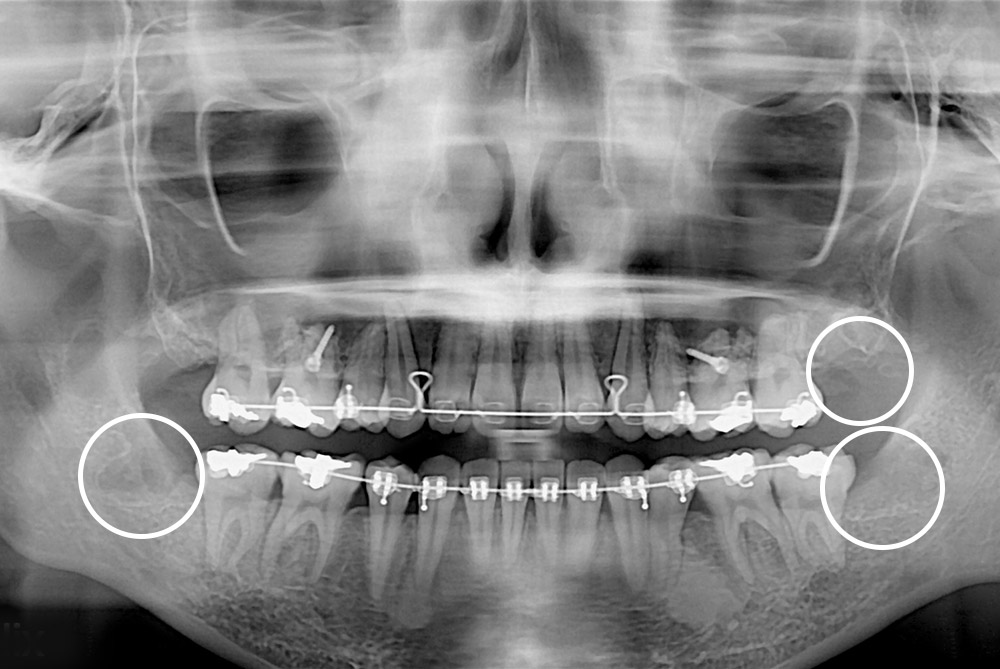

[사랑니] 매복 사랑니 발치

치료전 : 2019-01-11